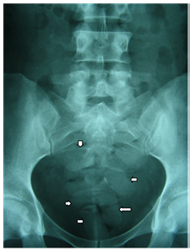

There are so many of these sent out that if a few don’t make it, there is no consequence to the drug barons because they make such a vast profit that such a loss is worthless. The methods above are for cargos of larger amounts of cocaine but there are other methods where the cocaine is concealed and trafficked in smaller amounts. Common methods are body stuffing and packing24 where drug mules are used to traffic cocaine through customs. Cocaine is the most common drug involved in body stuffing25 and it poses serious risk to the drug mules.26 Figure 10 shows the cocaine pellets that have been swallowed by a body packer.

Figure 10 Image showing the pellets of cocaine inside a body packer.26

There can be up to two kilograms of cocaine swallowed in pellets at one time and lubricant jelly and tubes down the throat are used to aid the process. Although the medical risks are serious there is also the risk of imprisonment but this is not enough to stop the drug traffickers because their income takes priority over the extreme risks and they have to do this in order to make a living. Other methods of trafficking drugs are by using animals where pellets are forced into them, specially made suits that have compartments to contain cocaine, putting it in luggage, and then some of the methods are so organised that the cocaine is actually concealed in the items at the point of manufacture such as paint, buttons of clothing, coal and compost.14 After researching the trade routes and trafficking methods it is clear that there is an established network in order to transport cocaine from South America to the rest of the world.